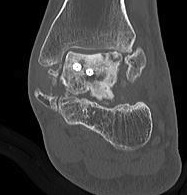

CT

Talus ACN CT 1Talus AVN CT 2